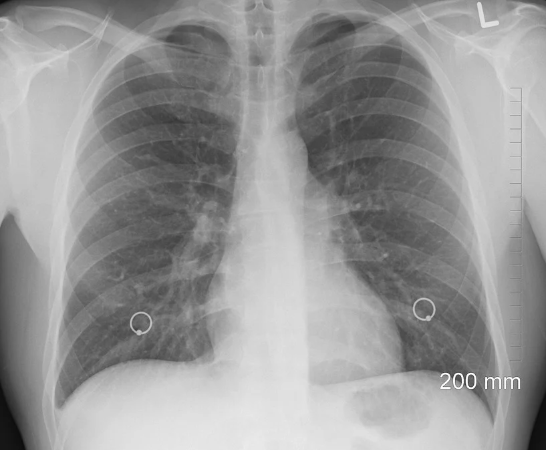

치명적인 이유1. 호흡기와 폐 질환

코로 숨을 쉬게되면 콧속 점막에서 분비되는 점액과 섬모들이 공기 속의 세균과 바이러스를 1차적으로 방어해주는 역학을 한다. 1차적으로 막은 후에 편도 뒤로 넘어가는 과정에서 또 한번 유해물질을 거른다.

하지만 입으로 숨을 쉬면 이런 두 단계가 생략되고 유해물질이 폐로 바로 들어갈 가능성이 높다.

이런 행동이 반복되면 폐 기능의 약화는 물론이고 호흡기 질환 등 각종 감염성질환에 취약해져서 감기나 폐렴에 걸릴 확률도 높아진다고 한다.